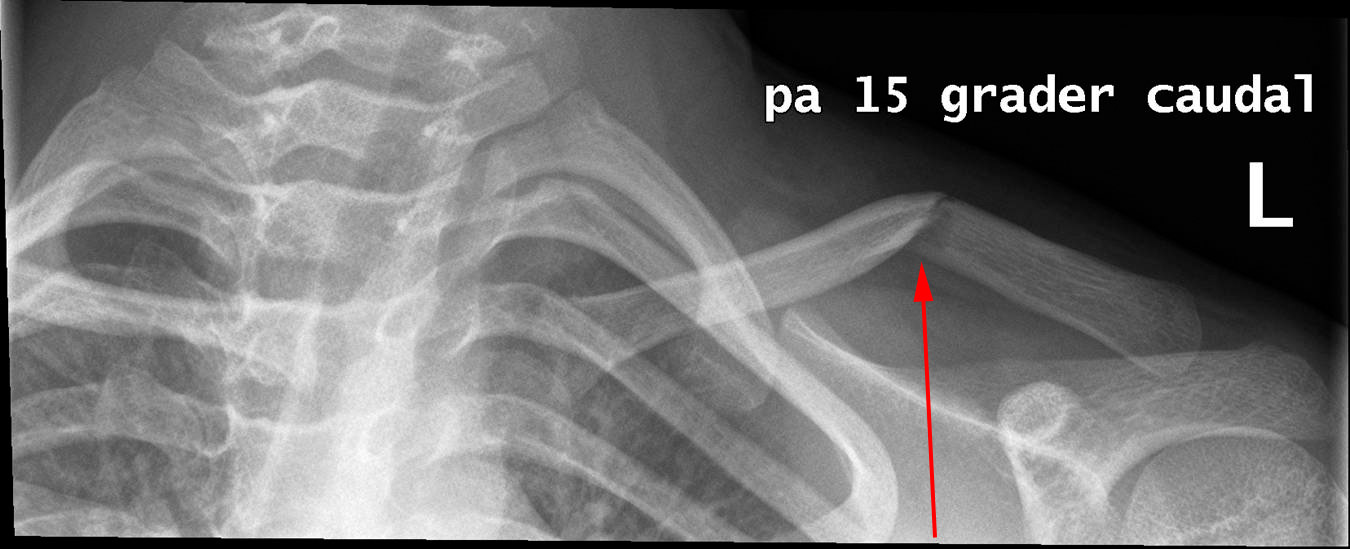

Brud (rød pil) på venstre kraveben (clavikel) efter fald.